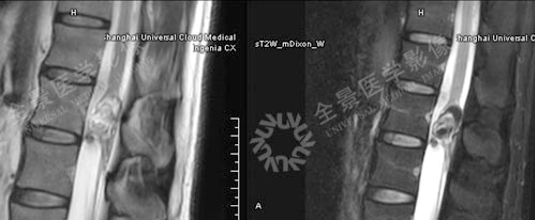

3. 骨关节

骨巨细胞瘤

T2WI不均匀等信号,PET/CT显示:软组织肿块,FDG明显摄取增高。

增强扫描明显强化